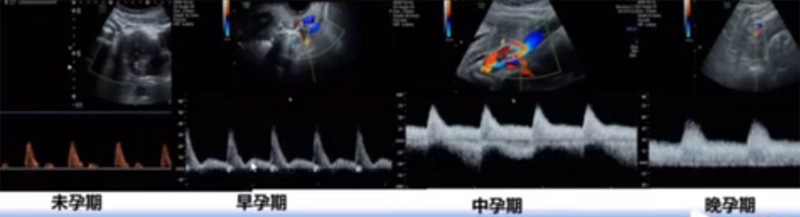

位于輸卵管的后下方,子宮兩側(cè)的后上方;借卵巢系膜與子宮闊韌帶后層相連。正常成人卵巢約4x3x2cm,跟睪丸的數(shù)值差不多,都是性器官,絕經(jīng)后卵巢萎縮變小、變硬。所以絕經(jīng)后婦女很難找到卵巢,主要功能:生殖和內(nèi)分泌功能分泌性激素。女性的第二性征。女性?xún)?nèi)生殖器的血管分布,動(dòng)脈有子宮動(dòng)脈,卵巢動(dòng)脈,陰道動(dòng)脈,陰部?jī)?nèi)動(dòng)脈。靜脈它是與動(dòng)脈伴行。重要了解的是子宮動(dòng)脈,子宮動(dòng)脈是髂內(nèi)動(dòng)脈前干的重要分支,妊娠時(shí)候血流速度會(huì)增加的,為無(wú)創(chuàng)性檢查胎盤(pán)血管阻力的方法。未孕期頻譜為高阻力低舒張波形;正常妊娠時(shí)血流速度增加,血流阻力下降。